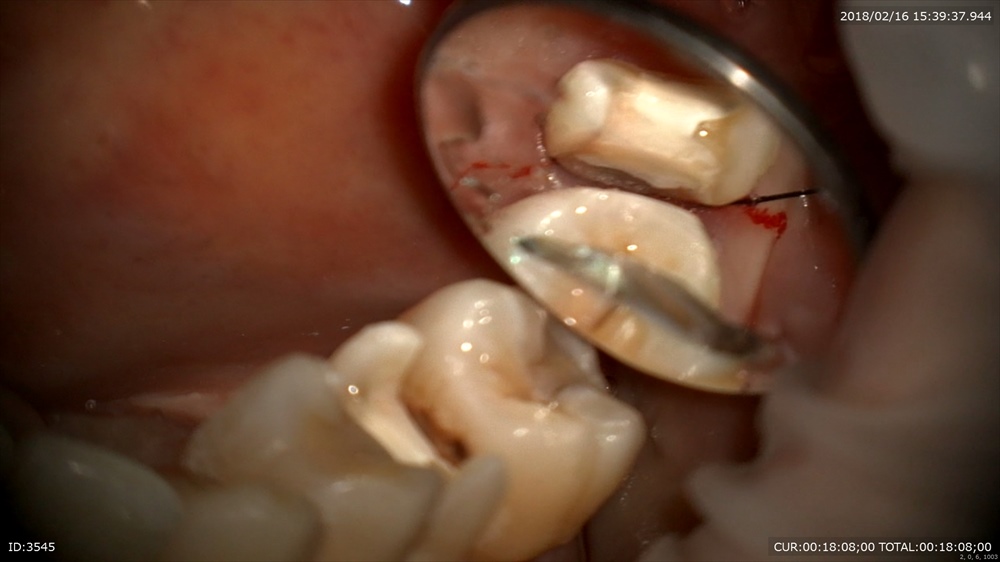

この歯の問題は縁下(歯茎より下に虫歯があること)でした

こんな時は圧排糸を2本

1本目

2本目

ラインを出す!

これで精密な型をとります!